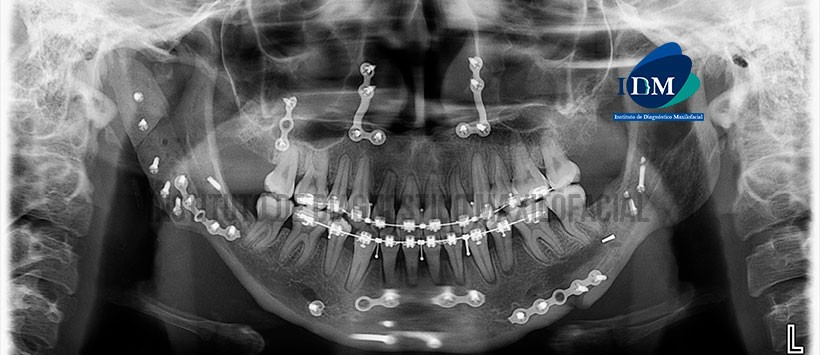

Paciente femenino de 21 años de edad, es referido al Instituto de Diagnóstico Maxilofacial (IDM) para por control tomográfico post quirúrgico de reconstrucción de ATM.

En la radiografía panorámica (Figura 1) se observa presencia de injerto óseo en zona condilar derecha asociado a tornillos de fijación quirúrgicas, además se aprecia placas y tornillos quirúrgicos en zona nasomaxilar, cuerpo, sínfisis y región para-sinfisiaria mandibular con presencia de aparatología fija para ortodoncia bimaxilar.